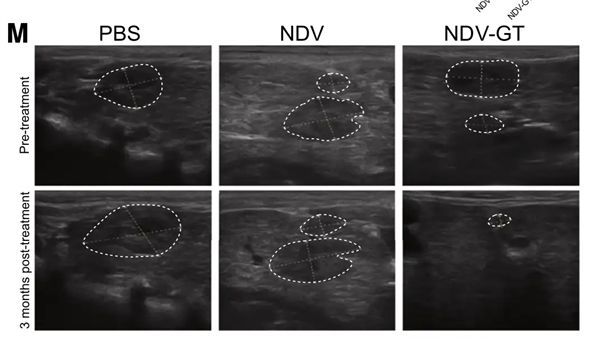

在猴子肝癌模型实验中,这种溶瘤病毒成功让肿瘤在 3 个月内完全消失,且没有严重副作用。

彩超显示 NDV-GT 治疗后猴子肿瘤消退甚至消失